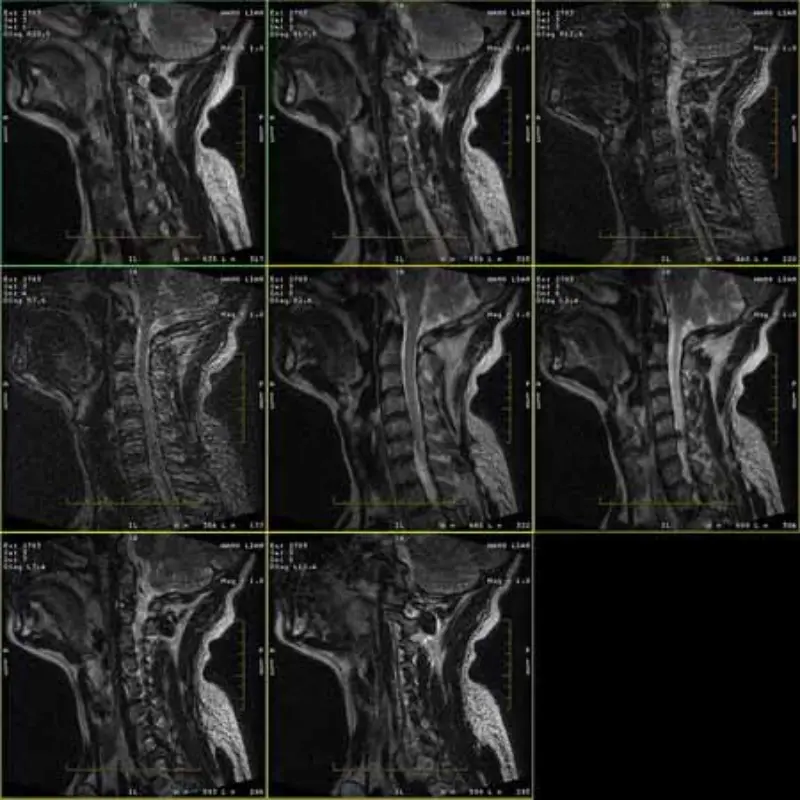

FRFSE र GRE प्रोटोकलहरूको छविहरूमा भूत छ र कहिलेकाहीँ कम SNR छविहरू एक श्रृंखलामा देखा पर्दछ। तर SE प्रोटोकल छविहरू सामान्य छन्।

कृपया संलग्न छविहरू हेर्नुहोस्।